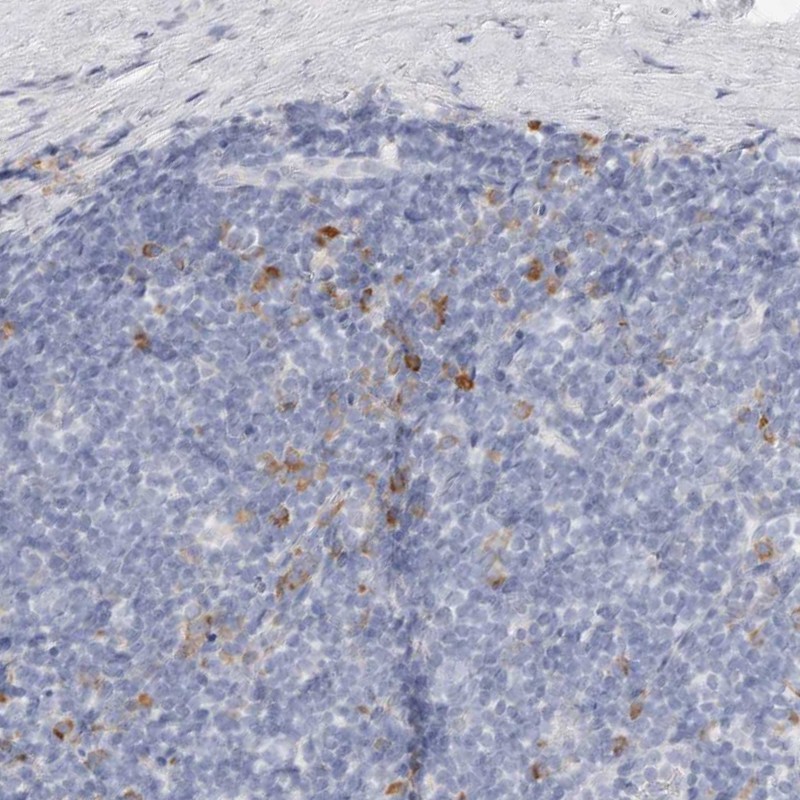

Immunohistochemical staining of human tonsil shows strong cytoplasmic positivity in germinal center cells.